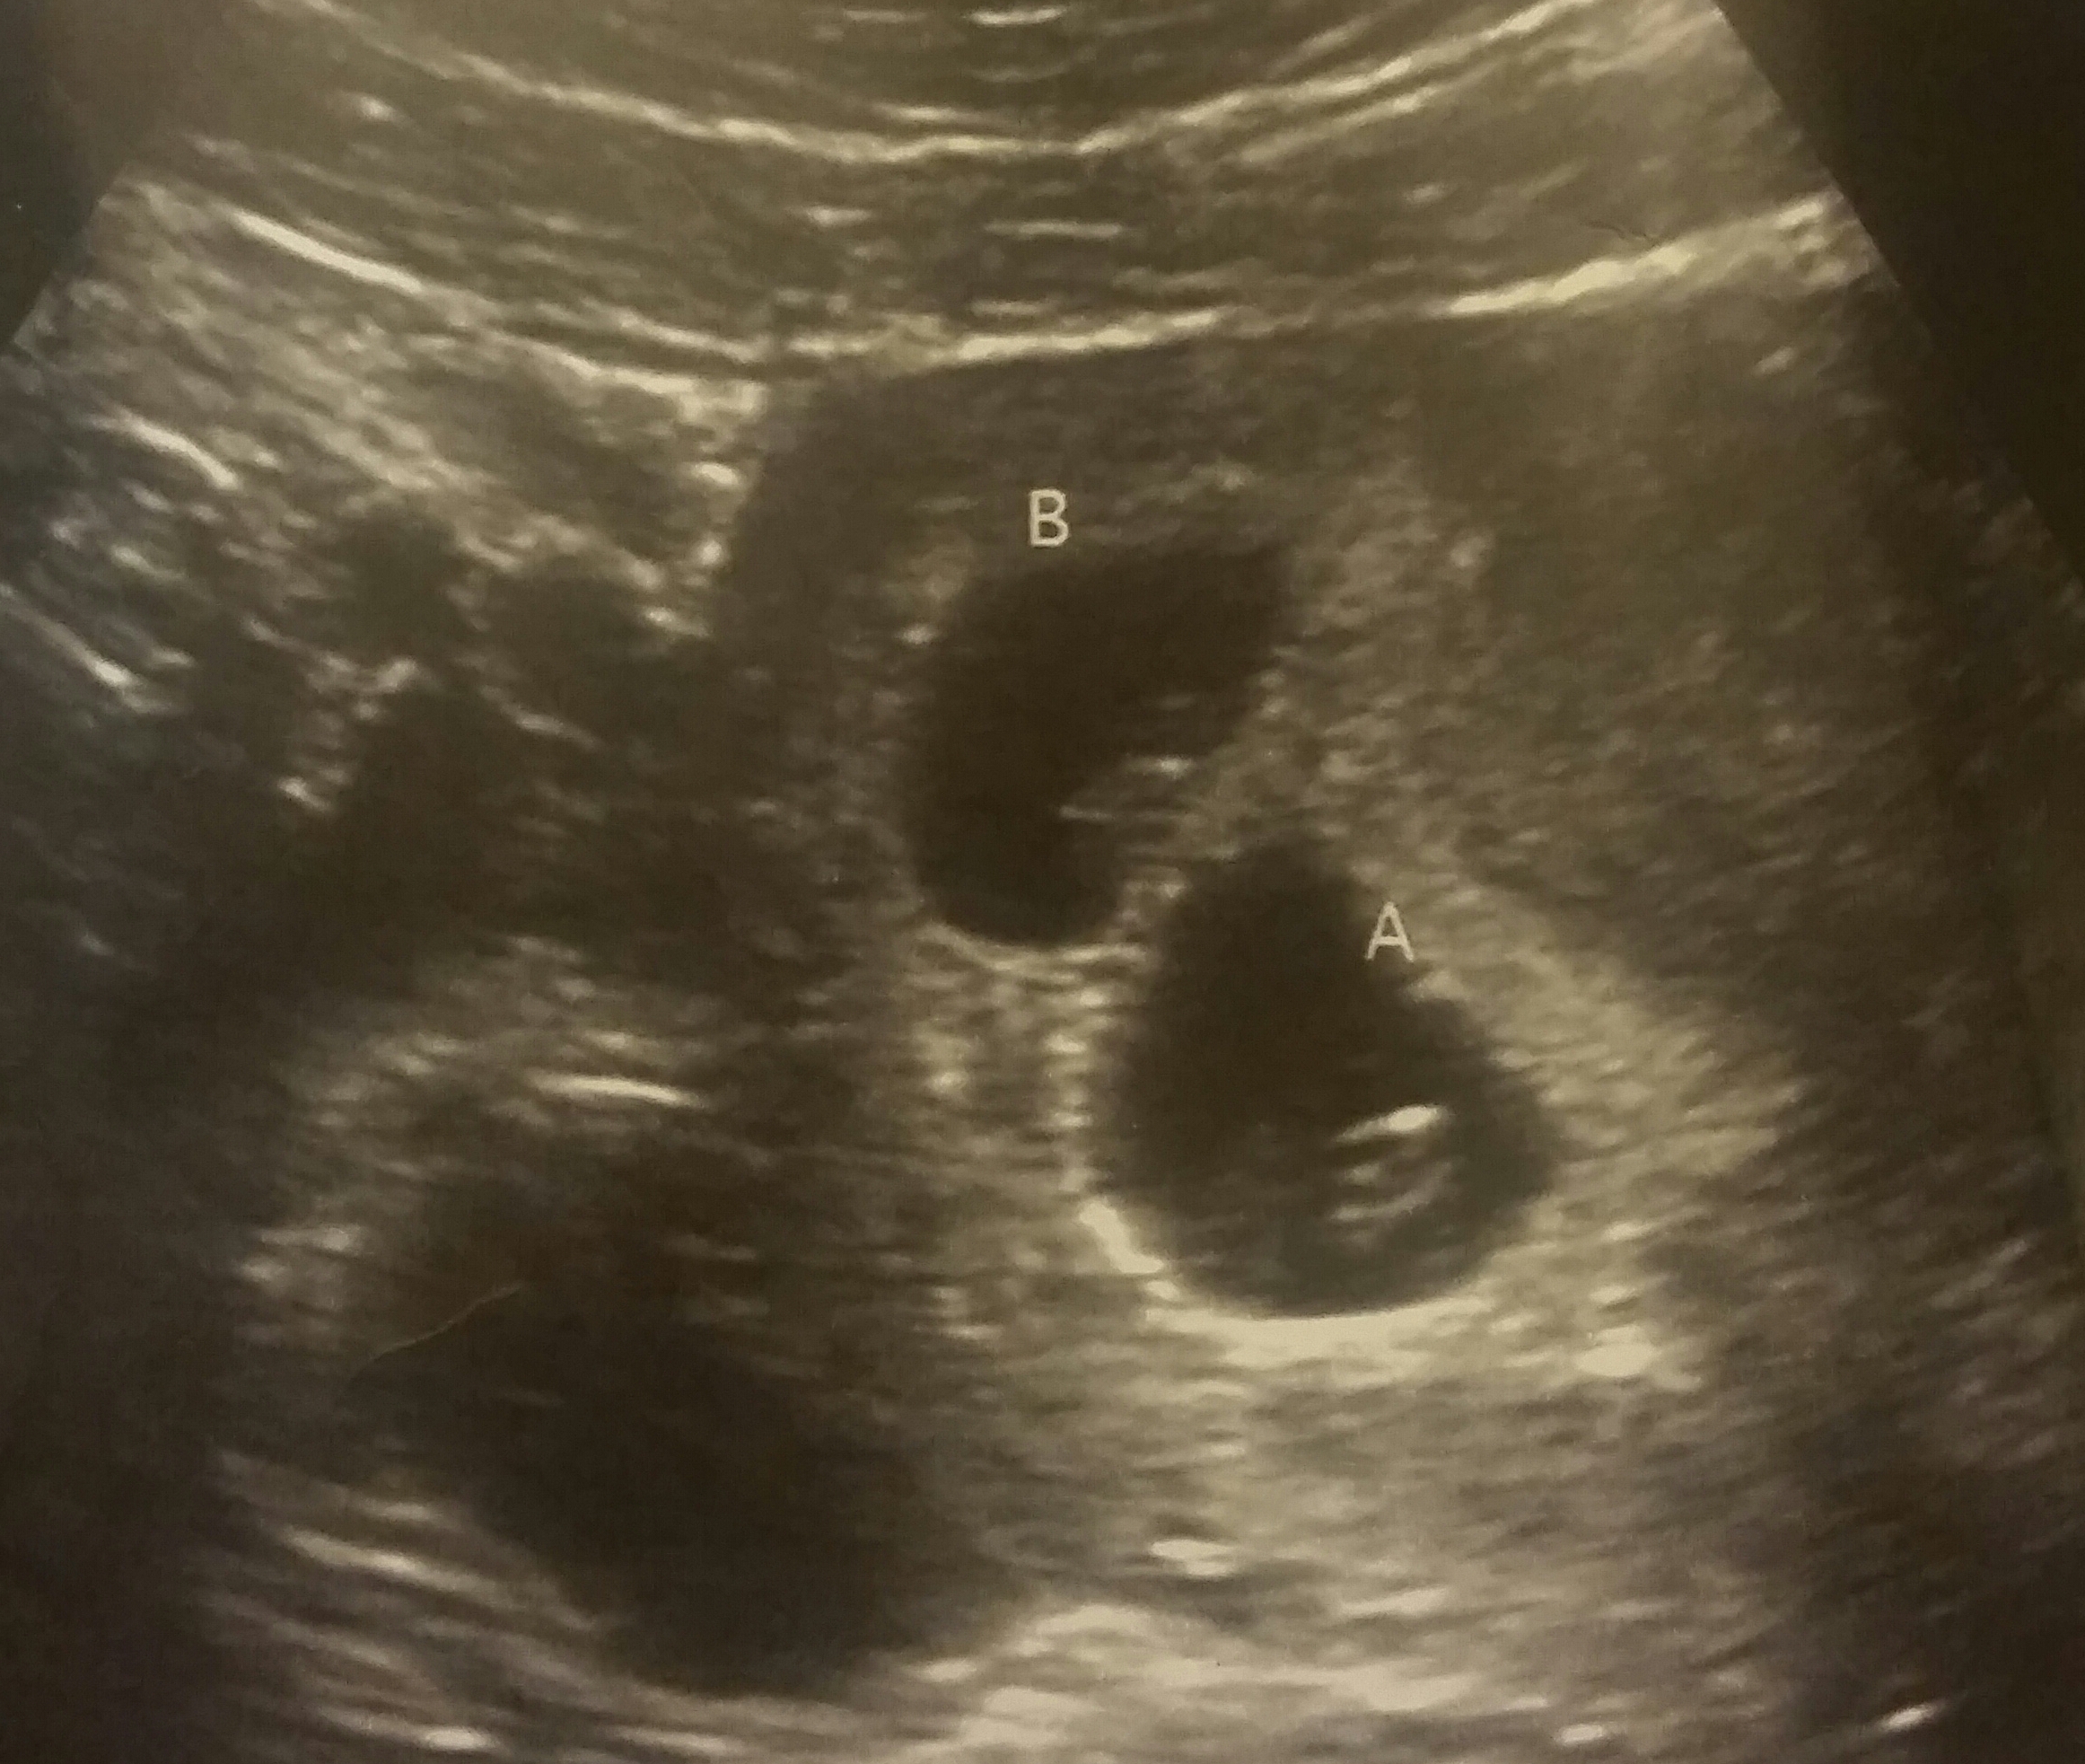

We had our first ultrasound on wednesday November 4th and to our suprise! It's twins! The tech turned to us almost immediately and said ummm there is two in there lol. Both babies 7wks 1day. Baby A heartbeat 158, Baby B hb 151